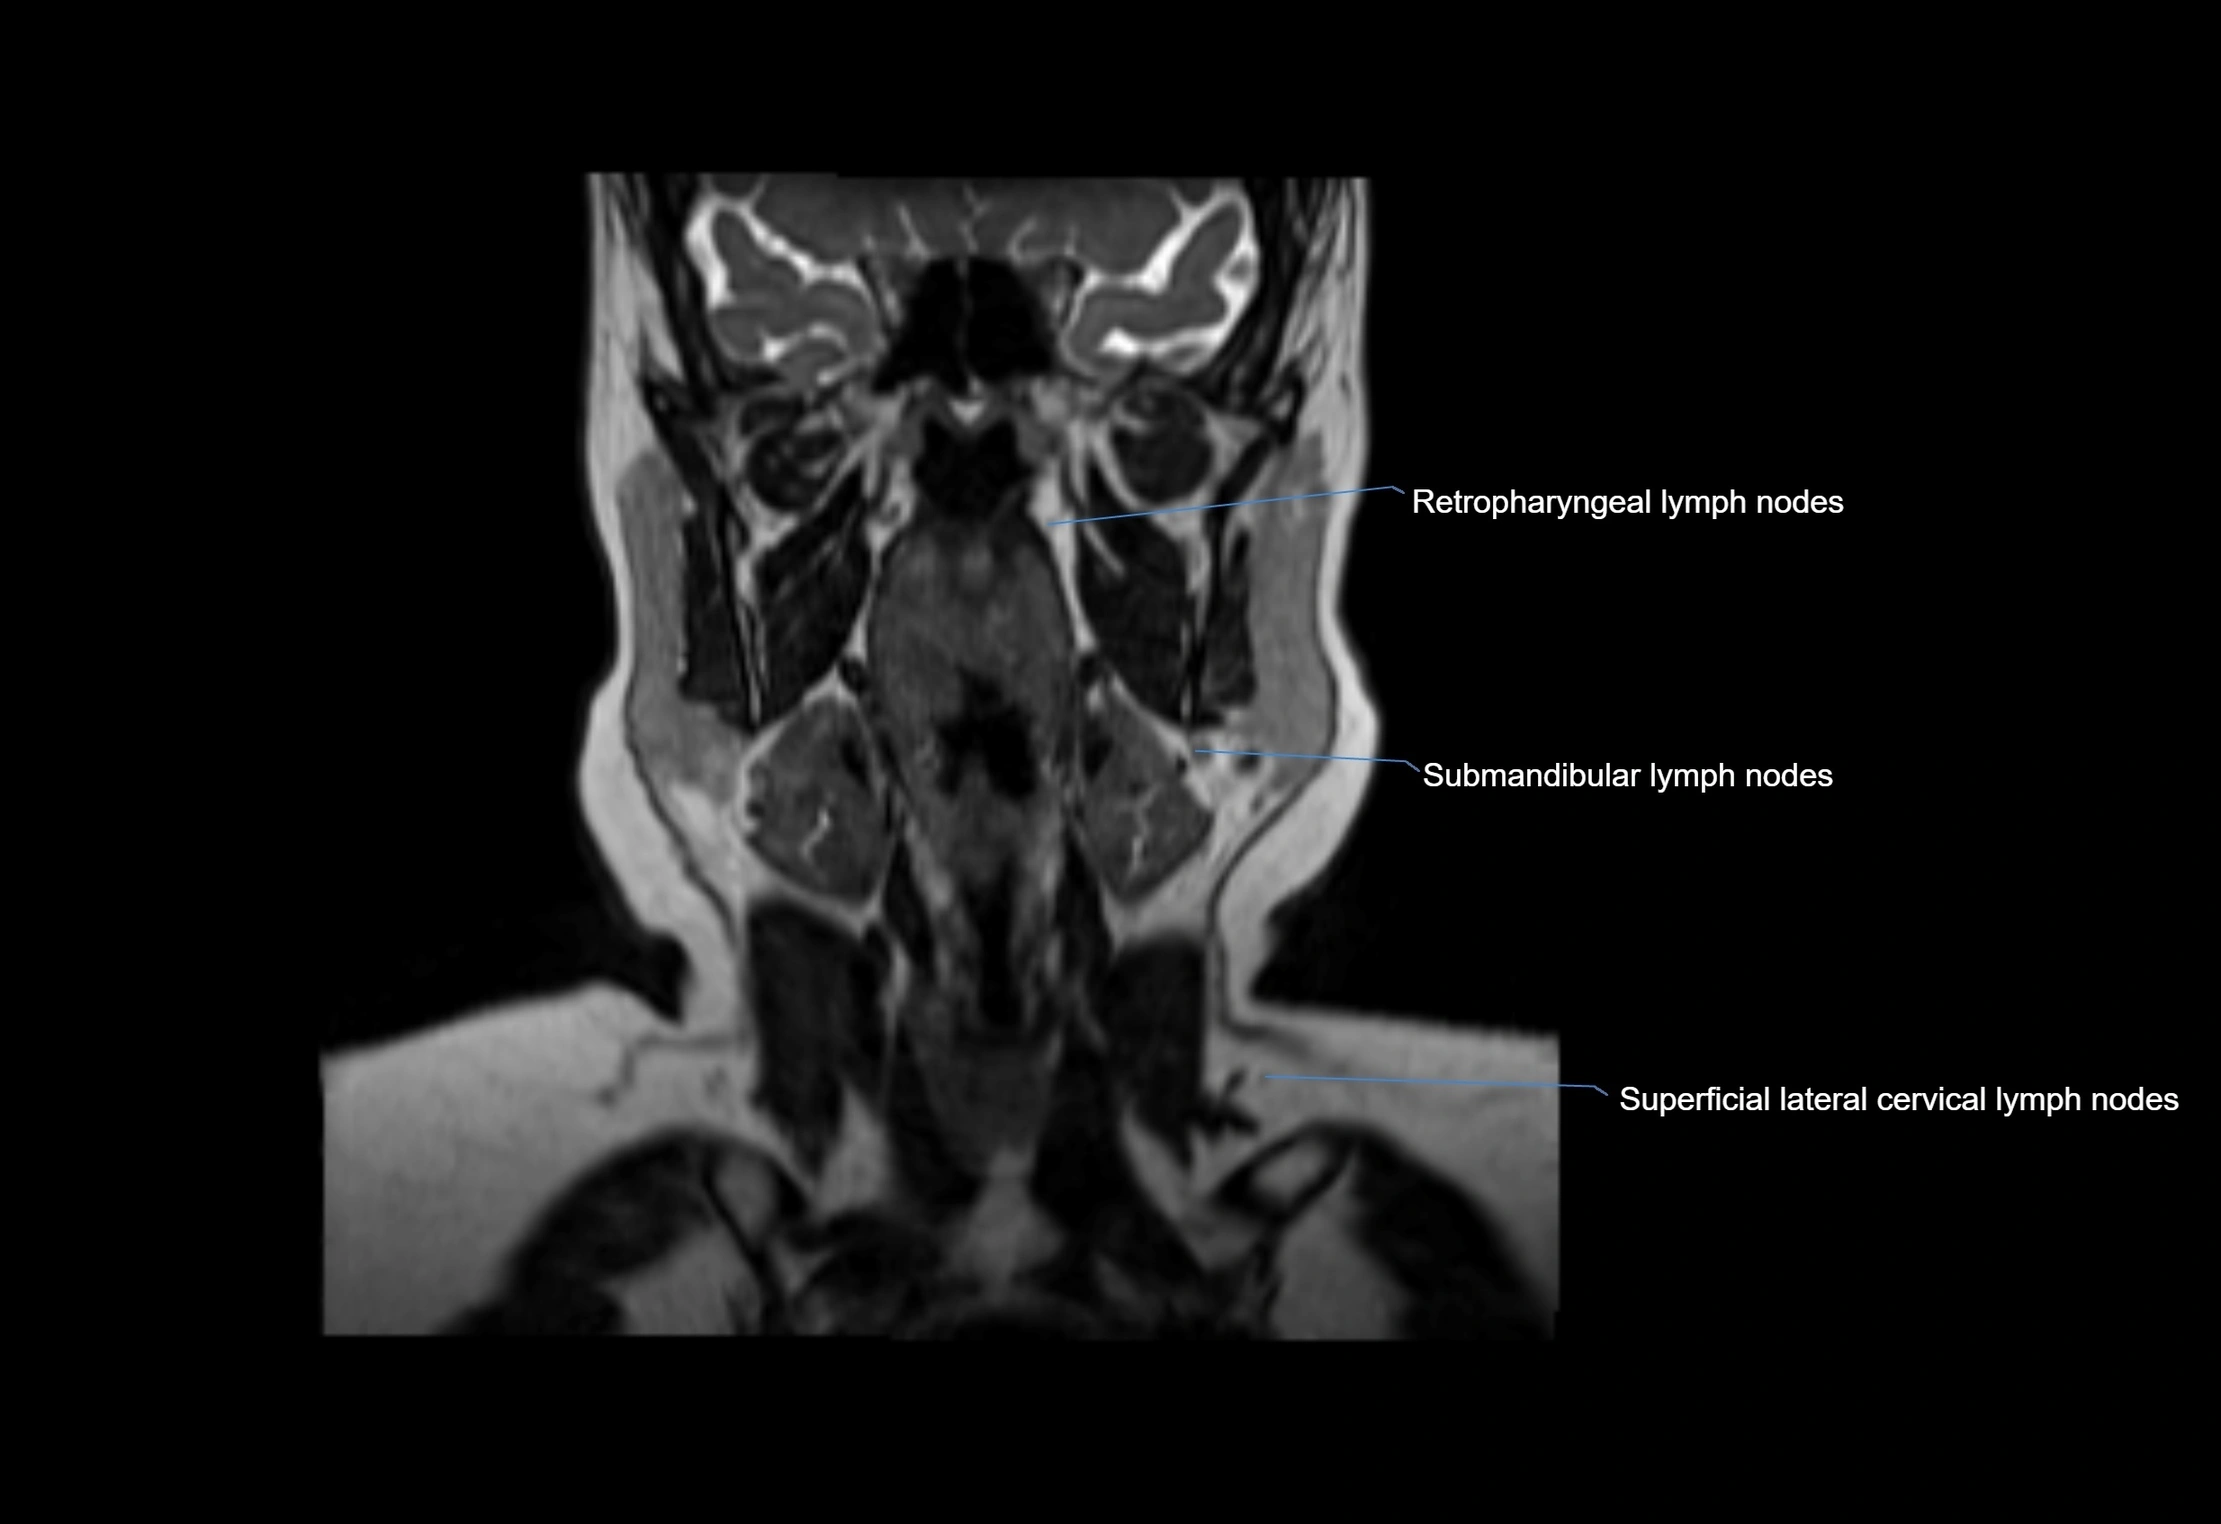

• Found along primary lymph node chains, including preauricular, submandibular, parotid, and occipital regions

• Embedded in subcutaneous fat or superficial fascia, often lateral or posterior to primary nodes

MRI Appearance

T1-weighted images:

• Normal accessory nodes appear as small, oval hypointense to intermediate signal structures within subcutaneous fat

• Surrounded by hyperintense fat, enhancing contrast for visualization

T2-weighted images:

• Nodes show intermediate signal, with surrounding fat bright

• Useful for detecting edema, inflammation, or infiltration

image